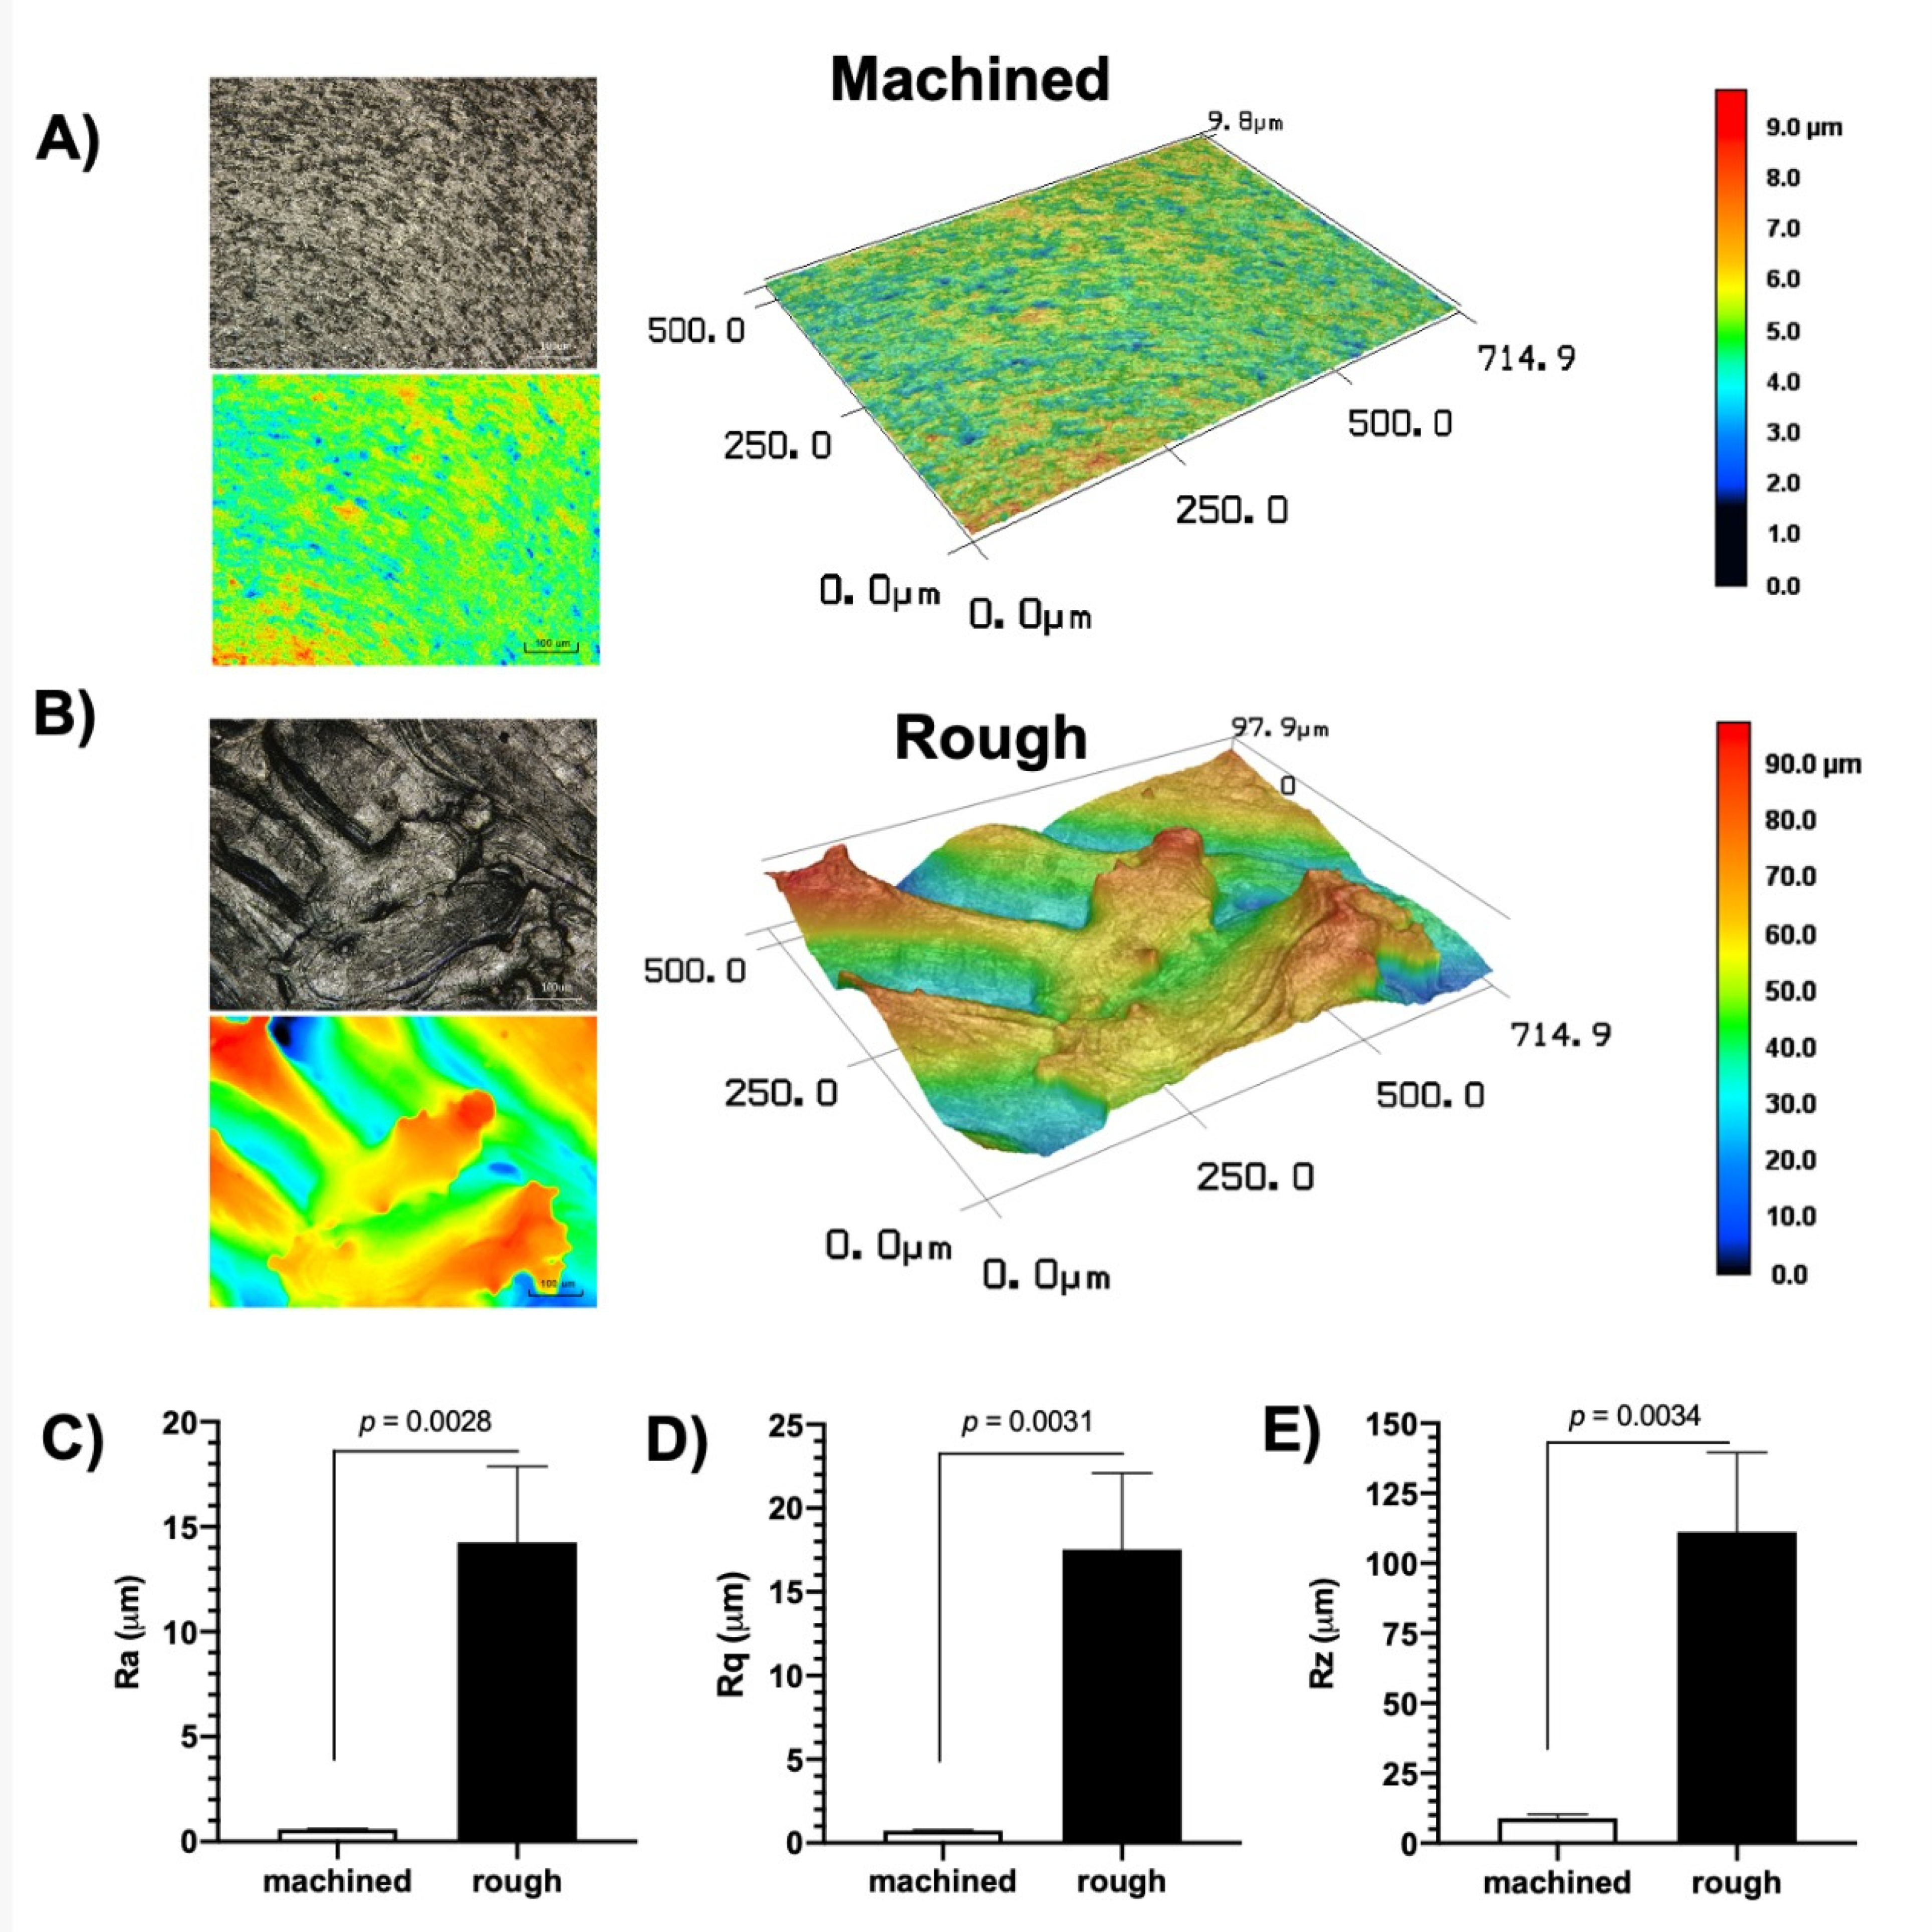

2.3. Abutment Surface Topography Characterization